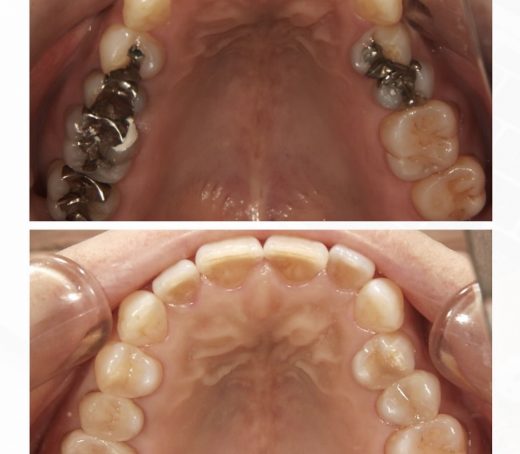

↓下の写真の、粒々と白く見えるポッチがアタッチメントです。

光で反射してますが、実際はあまり目立ちません。